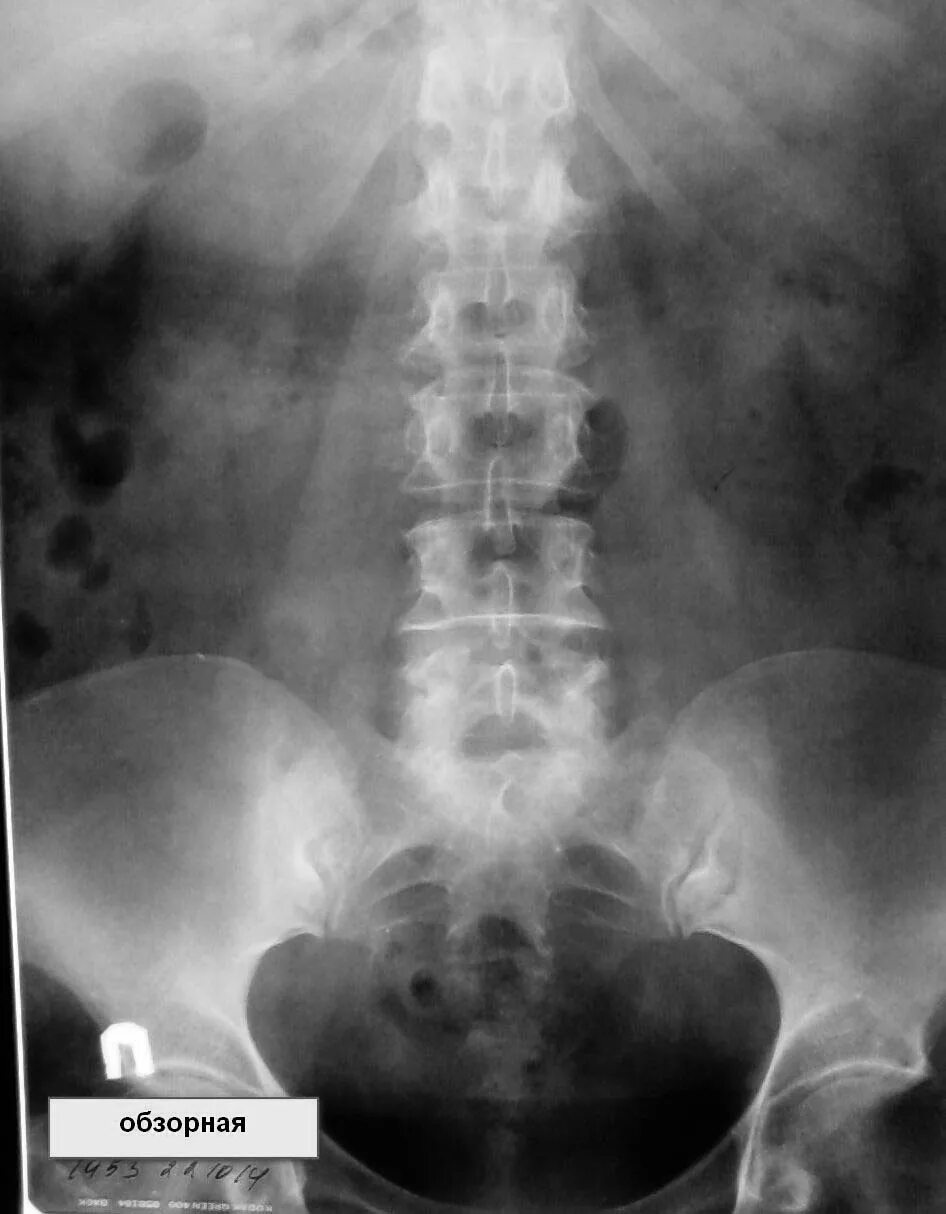

Как делается урография